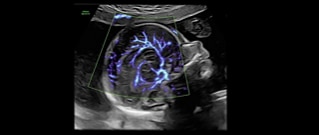

Next level color Doppler that delivers exceptional sensitivity for easy, fast visualization of blood flow, displaying a 3D like appearance as seen in this 27-week fetal heart.